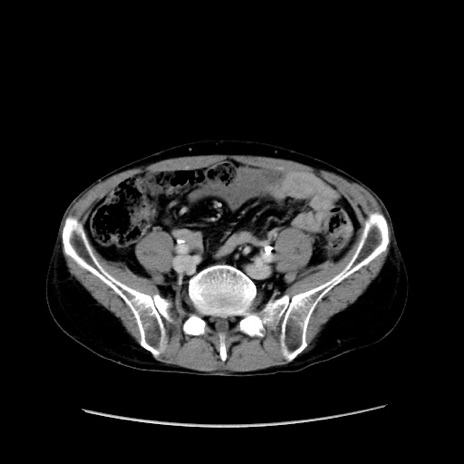

冠状断像